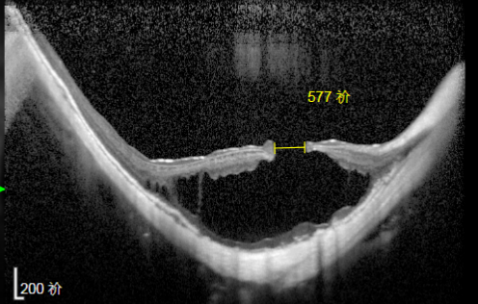

▶ 姜阿姨OCT检查黄斑部情况

通过检查,姜阿姨右眼后极部葡萄肿,不仅晶体完全脱位,而且已经呈现黑色落入内眼,阻挡视线,更严重的是黄斑区出现了板层裂孔,视力已降至0.06。